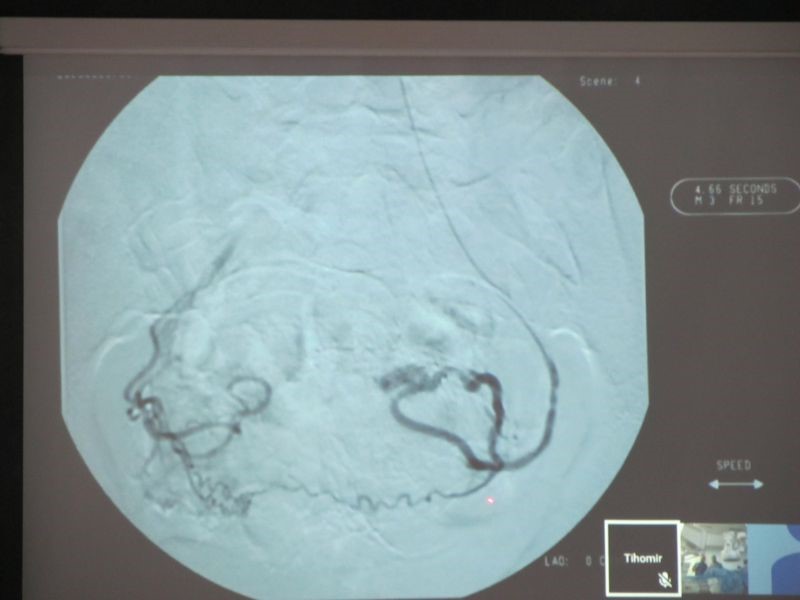

През последния месец в МБАЛ „Медика - Русе” бяха направени шест емболзации на пациентки с миома на матката. Всички те са на възраст между 40 и 50 години. Последните четири интервенции бяха извършени в събота преди обед, като всяка от манипулациите е с продължителност около 20-30 минути, а пациентките са в пълно съзнание. Чрез катетър през вена се достига до кръвоносния съд, който храни миомата. Изстрелват се микросфери, които спират притока на кръв и по този начин се ограничава развитието на образуванието. Част от пациентките изпитват болка в първите 24 часа след манипулацията, но това е напълно нормално. Екипът на болницата има специално обучен анестезиолог, който да влива венозно необходимите медикаменти за облекчаване на болката, и максимален комфорт на пациентката, допълни доц. Вълчева.